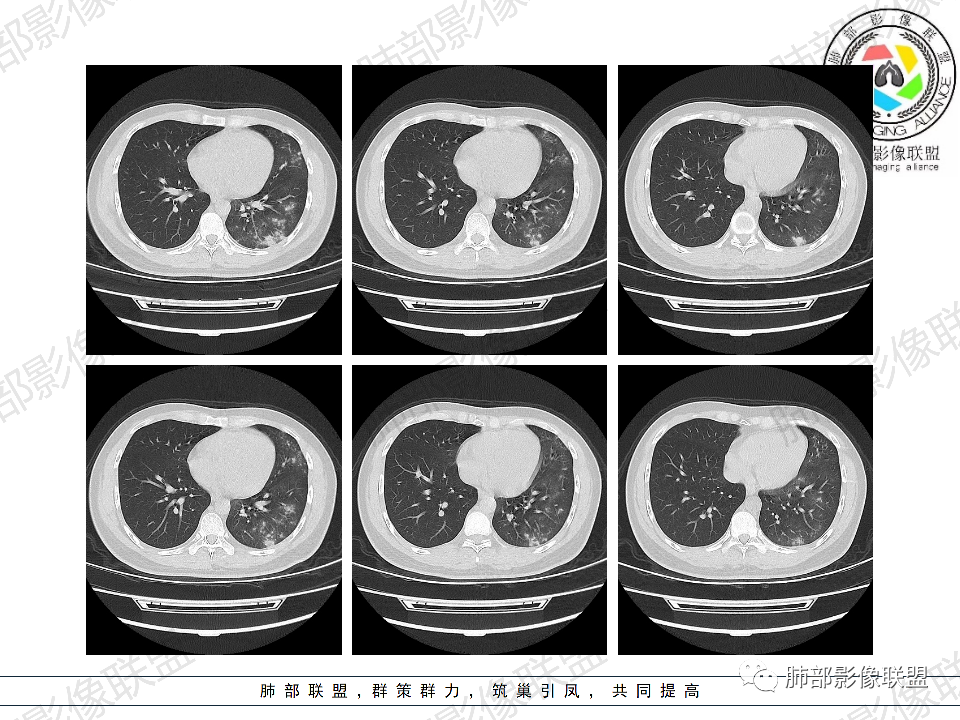

年轻男性,有HIV病史,免疫力缺陷病史,CD4明显减低,左肺胸膜下多发大小不等结节影,部分侧向融合,平行于胸膜,周围伴有模糊的GGO,部分结节与血管相连,血管束增粗,考虑隐球菌,建议查隐球菌荚膜实验,脑脊液隐球菌荚膜,鉴别:CMV(局限性比较少见)

年轻人,男性,HIV阳性,双肺多发斑片状,结节状阴影,以胸膜下分布为主,病灶与支气管血管束垂直生长,周围可见磨玻璃影,考虑肉芽肿病变,隐球菌感染可能性大,鉴别GPA,胞子菌肺炎。

双肺胸膜下多发大小不等结节伴晕征,部分似有融合

左肺多发大小不等结节影,部分融合,胸膜下分布为主,平行于胸膜,周围伴有磨玻璃晕,考虑隐球菌,鉴别:PJP

年轻男性,HIV阳性,胸闷喘憋,双肺胸膜下多发斑片结节影,周围伴晕,部分融合,白细胞低,CD4明显减低,考虑机会性感染性病变,隐球>PCP>结核

青年男性,HIV阳性,白细胞及淋巴细胞显著降低,CRP增高,胸闷气喘一周,影像为双肺胸膜下平行于胸膜分布的多发大小不等结节伴晕,单从影像上看,隐球是要首先考虑,但是不好解释临床症状。需要鉴别:1、曲霉所致IPA,临床有粒缺基础,胸闷一周要考虑,但影像不是典型的血道或气道分布又存疑,2、马尼,CD4低,HIV基础,要考虑,但是否有旅广史?另外纵隔淋巴结无肿大,肝脾不肿大,可能稍小。3、PCP,HIV基础,CD4低,胸闷气喘要考虑,影像分布不典型。4、腺病毒或EB病毒感染,HIV基础,影像改变要考虑,但是发病无发热,存疑。5、结核,临床与影像均不典型。可能小。综上,隐球>曲霉>PCP>马尼>病毒感染。下一步,查隐球荚膜抗原,NGS找病原体。

我们科里读片的时候,也是觉得主诉特别像PCP的主诉。但是影像学表现,双肺胸膜下多发小结节,结节周围带晕,蘑菇兄弟手拉手,有的结节侧向融合整体与胸膜平行。影像符合隐球。我们科里艾滋合并隐球菌真正确诊出来的很少。所以要说总结HIV合并隐球的病例特点,我没有发言权

肺隐球菌多分布在肺野外带或胸膜下区域,下叶多见,可能余隐球菌更容易在胸膜下肺泡中定植或蔓延有关;显示腺泡结节,然后取决于宿主免疫,可以入血,然后血播

如果是血播是随机分布,他这个是胸膜下

不是血道,就是直接吸入到远端肺泡

5、分布:病灶分布多位于胸膜下,可紧贴胸膜,也可与胸膜邻近,病灶长轴与胸膜平行。(划重点,分布特点非常重要)

8、晕征:病变早期可出现磨玻璃晕征,为周围炎性渗出或肺间质受累。

10、“葫芦兄弟”:邻近胸膜多发结节,形态密度类似,可簇状分布,较少多形性,没有新旧不等。